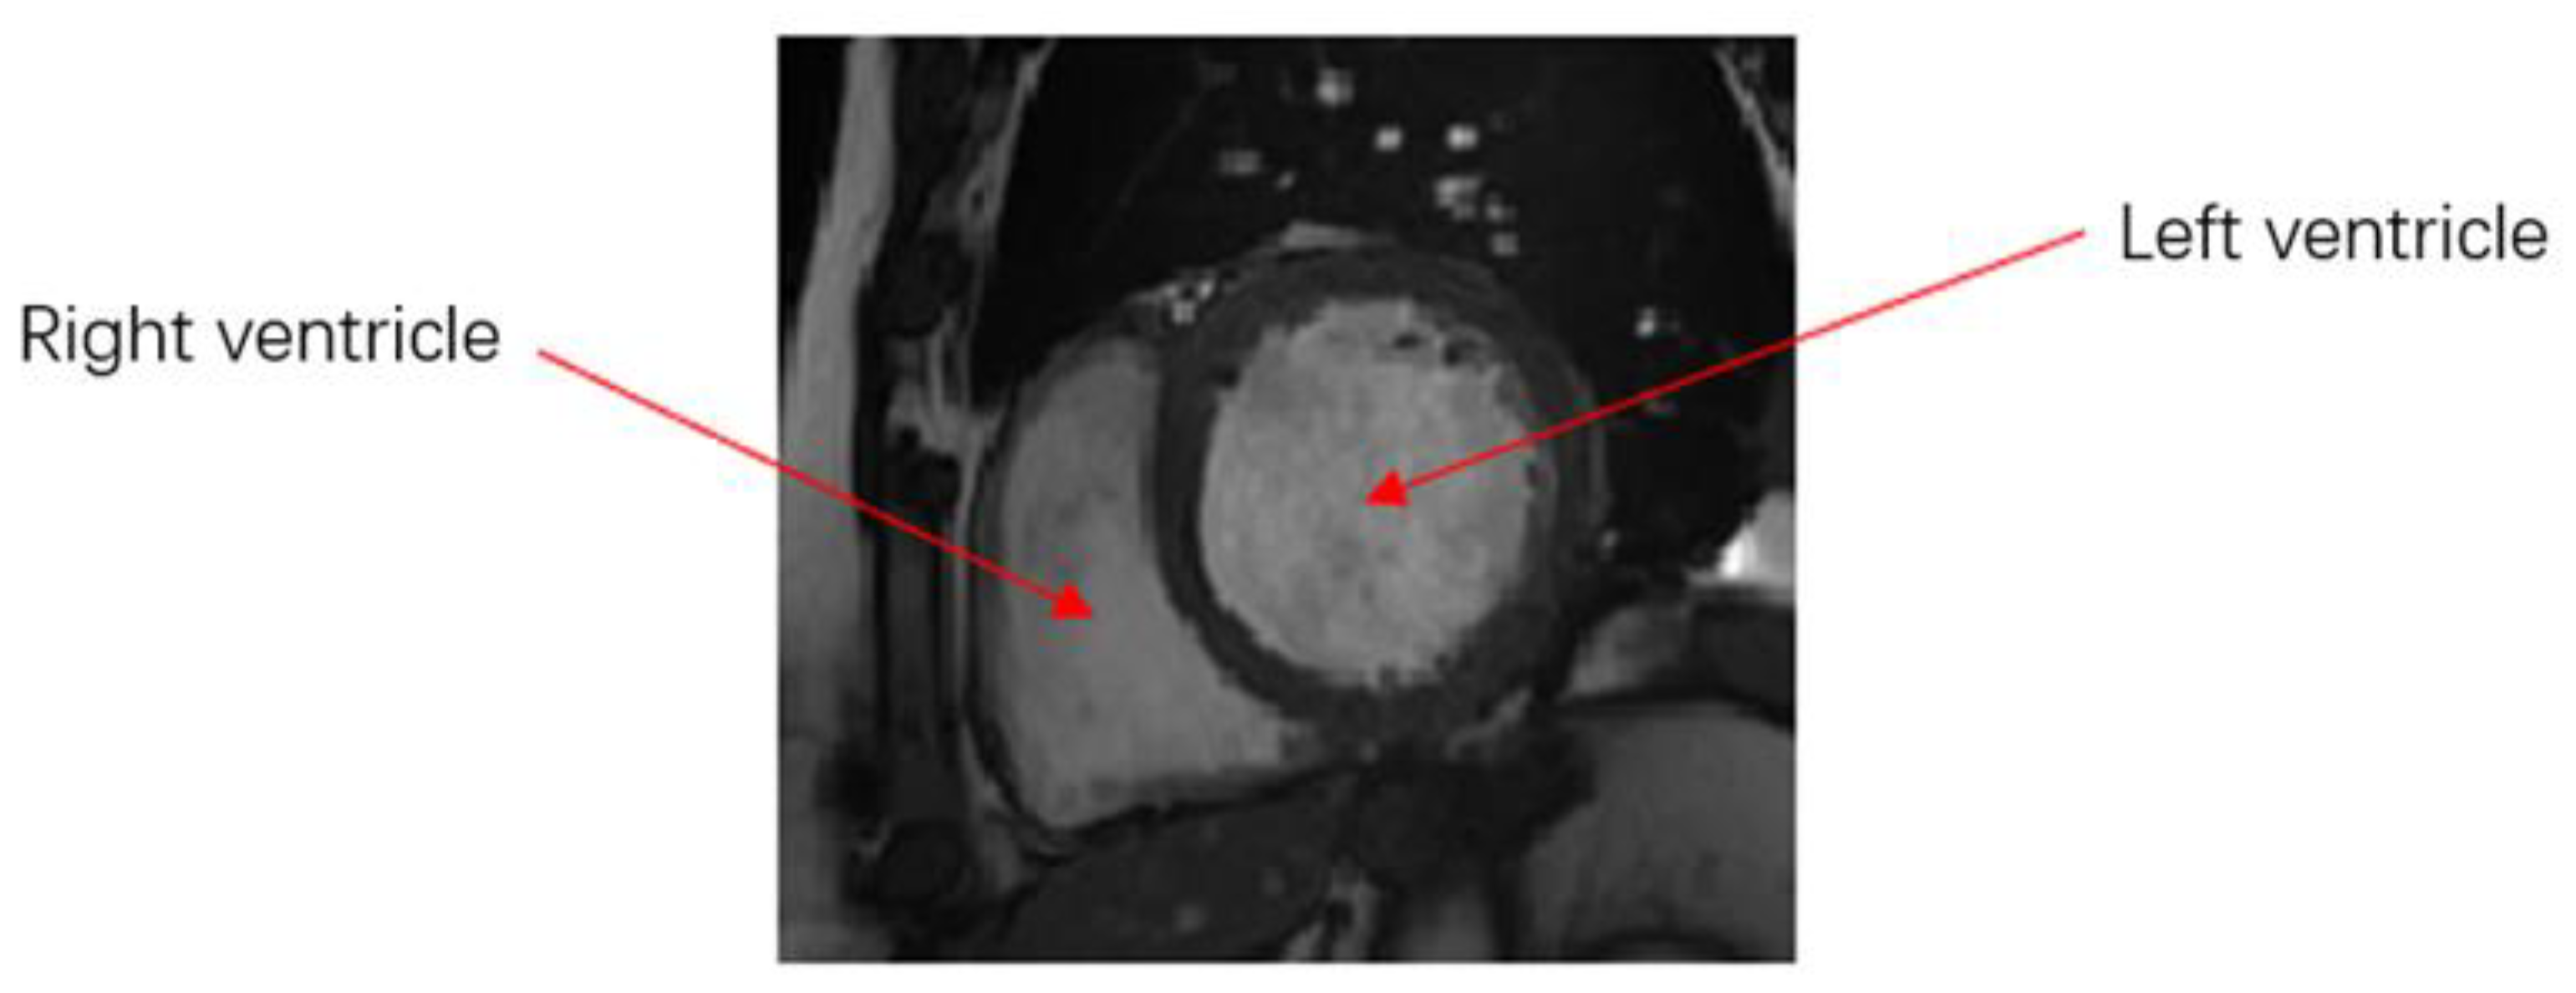

At present, cardiac MR imaging is one of the most important, accurate, and noninvasive diagnostic tools for imaging cardiac structure and function. Doctors usually analyze a patient’s cardiac MR images and calculate the continuous dynamic changes in the left and right ventricular volumes in the process of contraction and relaxation. This approach can be used to determine parameters, such as cardiac end-diastolic and -systolic volume, stroke output, and ejection fraction, to judge an individual’s cardiovascular health status. Therefore, accurate segmentation of ventricles in such imaging is very important. A cardiac MR image is shown in Figure 1.

Figure 1. MR image of the heart.